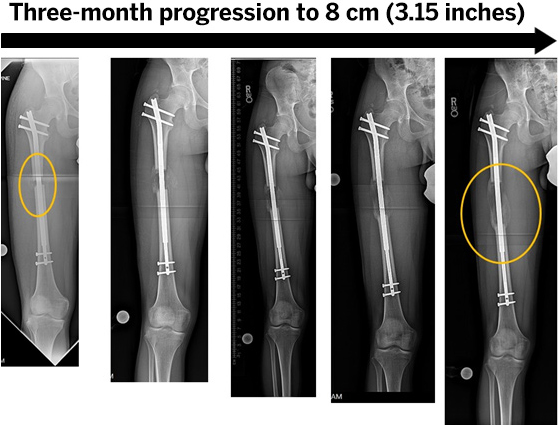

לאחר ניתוח להארכת גפיים, טיפול נאות לאחר הניתוח חיוני להחלמה מוצלחת. מטופלים בדרך כלל שוהים בבית החולים מספר ימים, ולאחר מכן טיפול פיזיותרפי רגיל כדי לקדם ניידות וחוזק שרירים. במהלך תהליך הריפוי, המכשירים החיצוניים או הפנימיים המשמשים להארכת העצמות מתרחבים בהדרגה, ומאפשרים לעצמות לצמוח. יש צורך במעקבים קבועים אצל המנתח כדי לעקוב אחר ההתקדמות ולבצע התאמות. ב-Healing Travel, אנו מבטיחים טיפול מקיף, כולל תיאום רפואי, תוכניות החלמה מותאמות אישית וסביבה נוחה למסע הריפוי שלך לחו"ל.